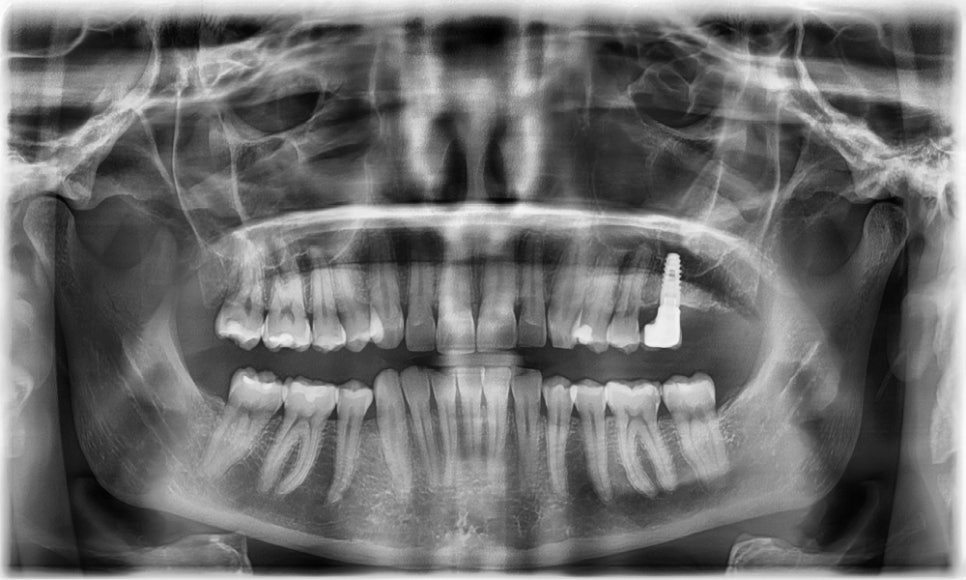

- 파노라마 엑스레이

위 앞니 두 개의 중 왼쪽 앞니의 사이즈가 오른쪽보다 살짝 커서 이 부분이 가장 불만이라고 하셨으며, 위아래 앞니에 약간의 치아 배열이 틀어져 있었습니다. 과거 하악 발치 교정으로 인해 하악 제1소구치가 발치되어 있었고 우측에는 공간이 약간 남아있었습니다. 또한 과개교합으로 인하여 아래 앞니는 거의 보이지 않는 상태였습니다. 왼쪽 제1대구치에는 임플란트가 식립된 상태였고, 제2대구치는 상실된 상태였습니다.